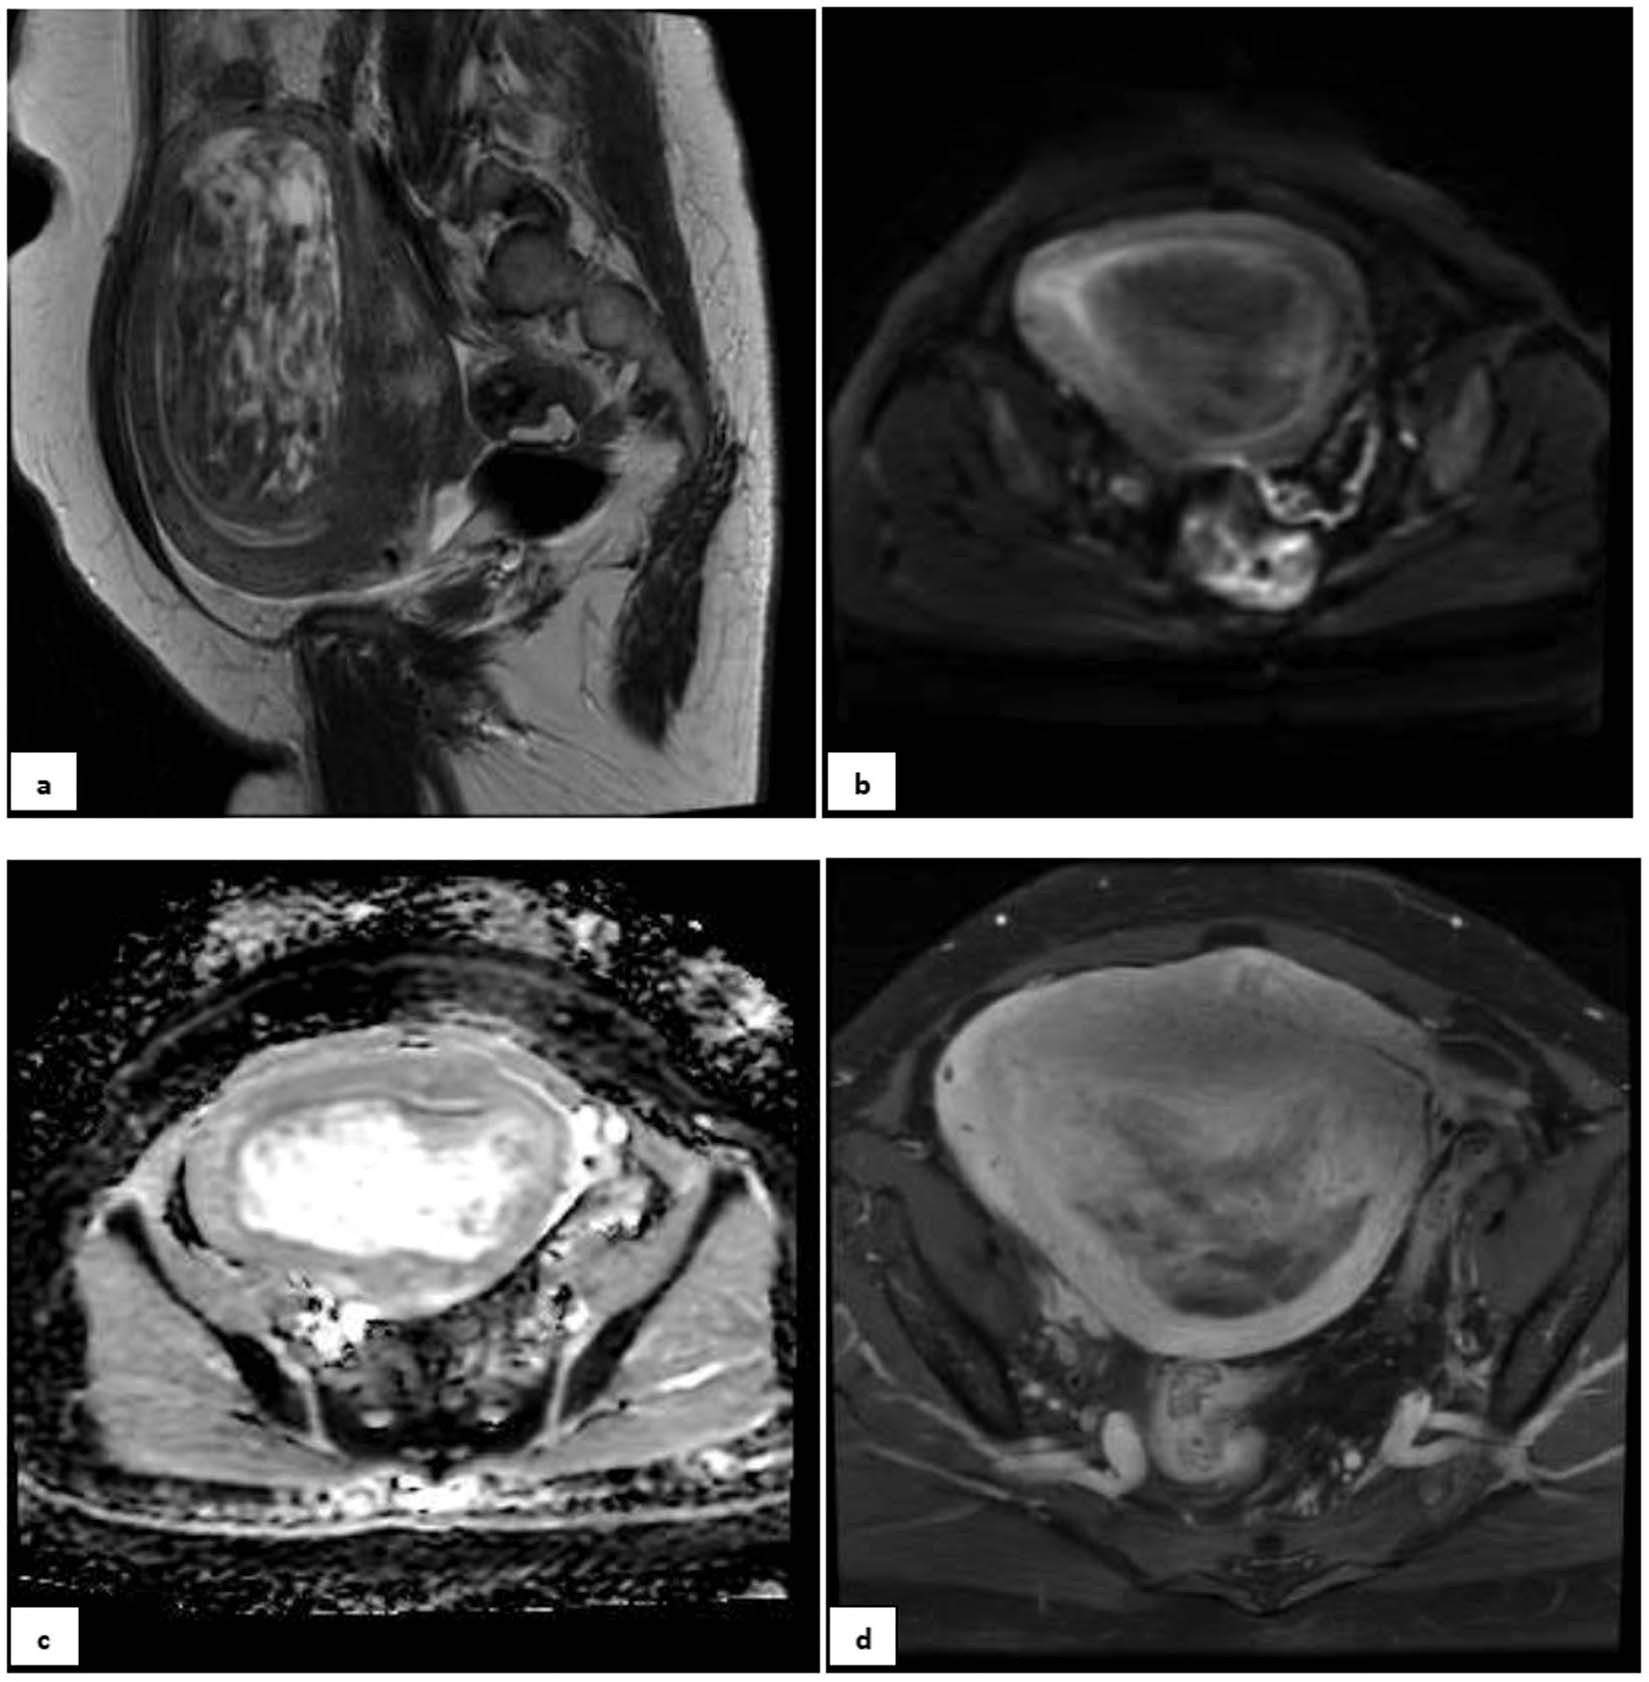

Figure 4

A 32-year-old nulliparous patient with 6 months of abnormal uterine bleeding and a heterogeneous myometrial mass on her ultrasound. (a) Sagital T2 MR-image detected a large predominantly hyper-signal lesion in posterofundal myometrium with anterior endometrial displacement; Tumor-Myometrial Contrast (TM) Ratio = 0.83; T2-scaled Ratio = 0.2 and T2 map = 42. (b) Axial DW image and (c) ADC revealed no evidence of restriction with mean ADC of 1.3 mm/s2. (d) Axial post-contrast T1 image in equilibrium phase showed the mass with mild enhancement significantly less than myometrium and without any central necrosis. Tumor-Myometrium Contrast Enhanced (TMCE) Ratio = −0.64. If we put this sample data in either of simple or complex decision-tree, the pathology could be predicted as “benign”. Eventually, the histo-pathological exam confirmed a benign tumor, degenerated leiomyoma.